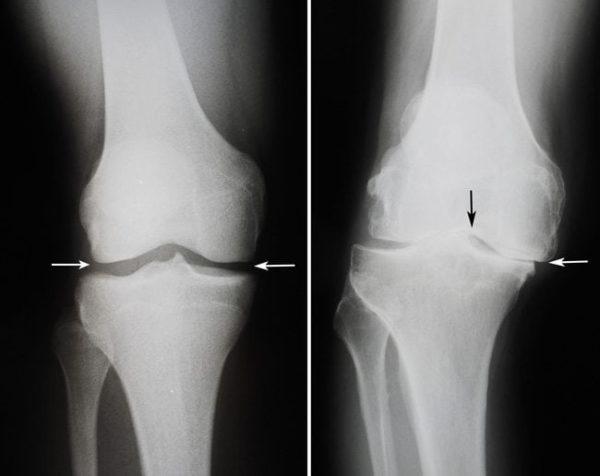

Артроз

Это разрушение внутрисуставного хряща колена и образования остеофитов, костных наростов. Артроз вызывает деформацию, сужение внутрисуставной щели и образованию анкилоза. Постепенно, без должного лечения, щель между суставами полностью исчезает, и он утрачивает свою подвижность.

Артрозом могут страдать люди в любом возрасте. На начальном этапе болезнь протекает незаметно, человек испытывает боль только после существенных нагрузок, которая затем сама проходит.

На второй стадии болевые ощущения начинают сопровождать человека ежедневно, возникает необходимость в приеме обезболивающих и противовоспалительных средств. Из-за боли амплитуда движений в колене уменьшается.

На последнем этапе происходит полное разрушение хрящевой ткани. Больной страдает постоянными болями, теряет способность к передвижению, помочь в данной ситуации может только операция.